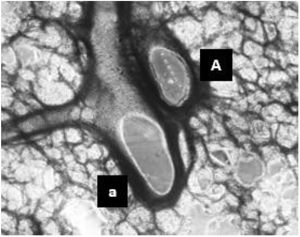

Figure 5 (above) shows fresh and thawed PCLS responses to endothelin application. Pictographs showing precision-cut lung slice samples with arteriole (a) and airway (A) components (left) and the selective and identical responses of arterioles in the fresh and thawed arterioles to endothelin application (right).

The lung represents a very complex intersection of the respiratory and vascular systems and resulting cytoarchitecture. AnaBios’ precision-cut lung slices accurately represent these components with high viability for successful downstream interrogation. PCLS samples show greater than 90% viability upon thaw and contain both respiratory and vascular components.